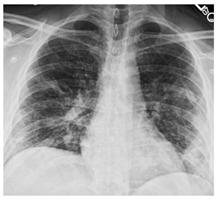

Стандартная РГ имеет низкую чувствительность в выявлении начальных изменений в первые дни заболевания и не может применяться для ранней диагностики. Информативность РГ повышается с увеличением длительности течения пневмонии. Рентгенография с использованием передвижных (палатных) аппаратов является основным методом лучевой диагностики патологии ОГК в отделениях реанимации и интенсивной терапии (ОРИТ). Применение передвижного (палатного) аппарата оправдано и для проведения обычных РГ исследований в рентгеновском кабинете. В стационарных условиях относительным преимуществом РГ в сравнении с КТ являются большая пропускная способность. Метод позволяет уверенно выявлять тяжелые формы пневмоний и отек легких различной природы, которые требуют госпитализации, в том числе направления в ОРИТ.

4. Все выявляемые при лучевых исследованиях признаки, включая КТ-симптомы, не являются специфичными для какого-либо вида инфекции и не позволяют установить этиологический диагноз. Вне клинической (эпидемической) ситуации они не позволяют отнести выявленные изменения к пневмонии COVID-19 и дифференцировать их с другими пневмониями и невоспалительными заболеваниями. Данные лучевого исследования не заменяют результаты обследования на РНК SARS-CoV-2. Отсутствие изменений при КТ не исключают наличие COVID-19 и возможность развития пневмонии после проведения исследования.